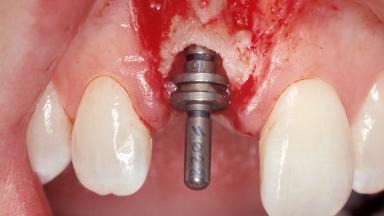

Immediate Placement of an Implant in a Maxillary Right Central Incisor Site

A 30-year-old female patient was referred to the office for the treatment of tooth 11. Her chief concern at the initial visit was to inquire, “Why is my tooth pink?” Upon clinical examination, it was determined that tooth 11 had a previous history of trauma and that the clinical crown had become noticeably pink in color as a result of internal resorption. This diagnosis was confirmed radiographically, indicating a large radiolucency involving the central and distal portions of the clinical crown. It was determined that restoration of this tooth was not possible, and that extraction was indicated. The presence of a mid-line diastema, which the patient wanted to reproduce, directed the treatment plan for tooth replacement utilizing a dental implant.

Placement Protocol Immediate implant placement

Tooth Site Maxillary incisor or canine

Socket Morphology Single-root socket

Socket Integrity Sufficient, with intact bone walls

Bone Volume Sufficient, with intact walls